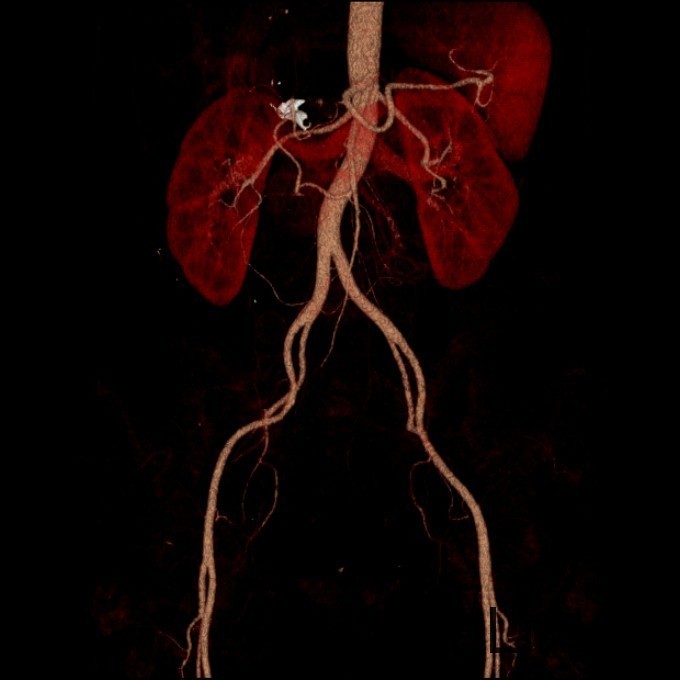

查体:神清,一般情况好,无水牛背、满月脸,皮肤无紫纹。 辅查:全腹CT平扫+增强提示右侧腹膜后区占位性病变,畸胎瘤可能性大。

诊断:畸胎瘤 治疗:入院后完善术前相关检查,查无手术禁忌后于全麻下行经腹腔镜腹膜后肿物切除术,术程顺利,术后无特殊,术后病理示:符合成熟性囊性畸胎瘤。

讨论:本例畸胎瘤因发生在肾上腺区,因此表现为发作性高血压。一般只要在CT图像上看到钙化、脂肪密度等特征性征象,增强扫描实性成分轻度强化,畸胎瘤的诊断一般不难。不过非成熟性的畸胎瘤一般缺少钙化和脂肪成分,此时要与腹膜后其他来源的实性肿瘤相鉴别。本例病理大体能够看到毛发,也是畸胎瘤比较特征性的病理表现。